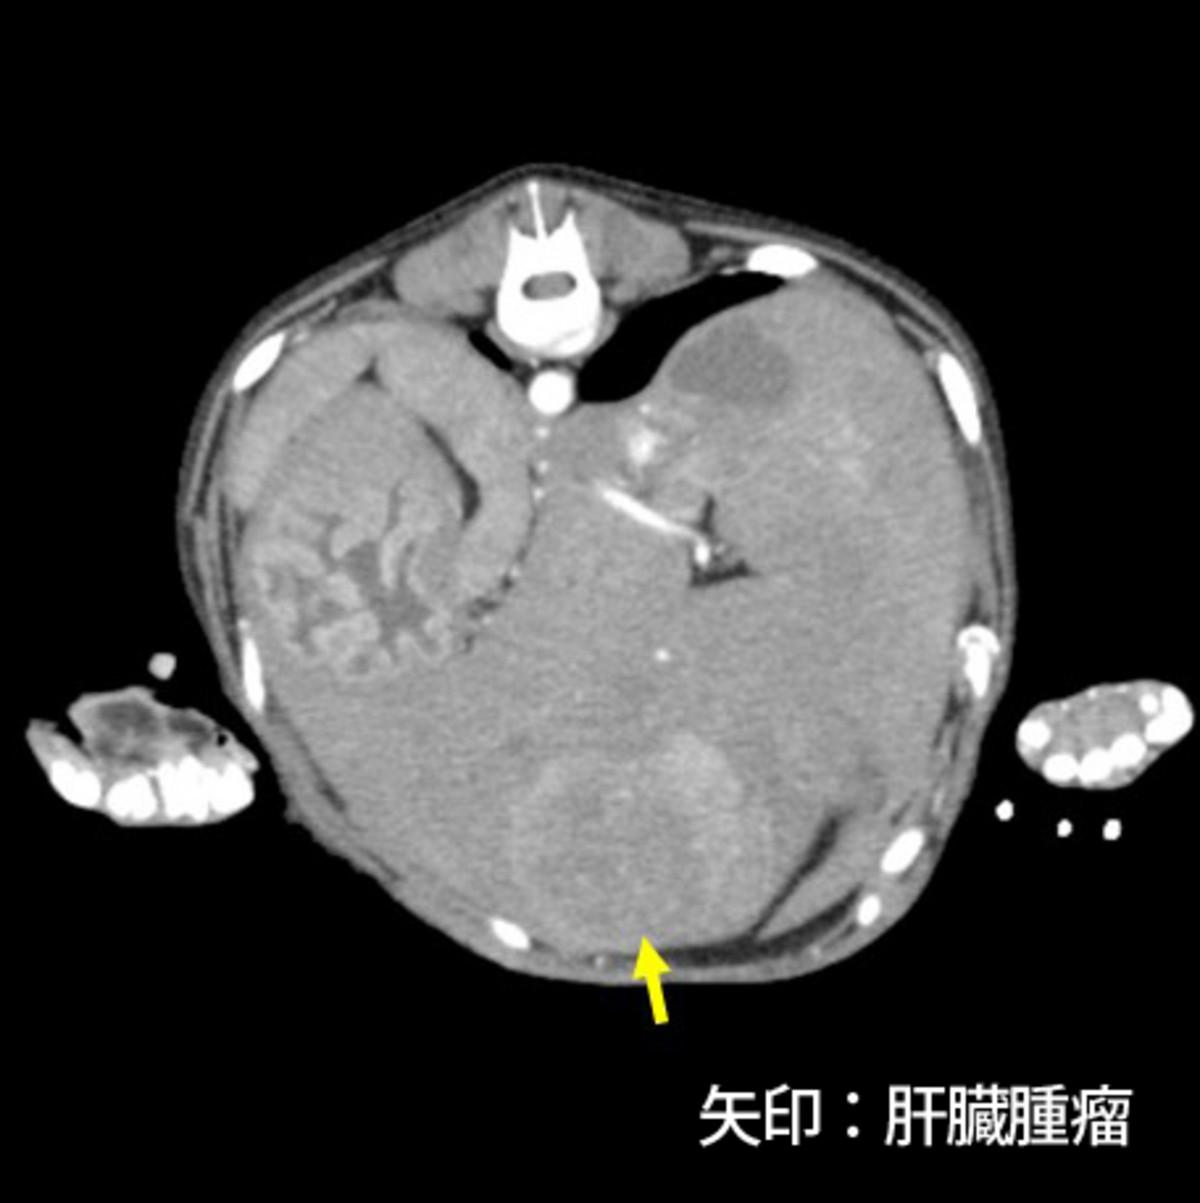

症例はミニチュア・ダックスフント、避妊雌、12歳11ヵ月齢、5.2kgです。当院初診の20日前に痙攣、失禁、意識の低下が5分ほど持続し、近医を受診しています。院内の検査にて低血糖(41mg/dL)、インスリンの低値、肝臓腫瘤を認め、ACTH刺激試験の結果から副腎皮質機能低下症は除外され、頻回の食事と糖液の投与により一般状態を維持していました。初診時の血液検査では低血糖(36mg/dL)および肝臓内側左葉に腫瘤を認め、糖液を経口投与してからCT検査を行いました。CT検査では肝臓の内側左葉(長径90mm)、外側左葉、尾状葉に多発性の腫瘤を認め、脾臓にも腫瘤(長径15mm)を認めました(図3)。肝臓原発の腫瘍および腫瘍に随伴する低血糖と診断し、根治は不可能であるものの臨床症状およびQOLの改善を目的とした手術が予定されました。

図3.CT検査にて多発性の肝臓腫瘤(図3-1、3-2)、脾臓腫瘤(図3-3)を認めた